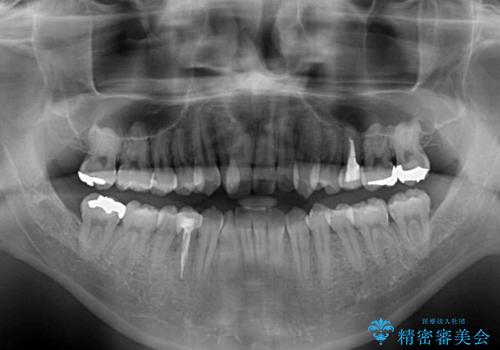

- 前歯のデコボコとクロスバイトを気にして来院された患者様です。

下顎の歯列弓に対して上顎歯列弓がやや小さく、側方の歯を中心にクロスバイトが見受けられました。

クロスバイトの改善は、インビザラインの場合歯髄壊死のリスクや咬み合わせが改善しきらないリスクがあるため、ワイヤー矯正をお勧めすることが多いですが、患者様の希望によりインビザラインにて矯正治療を行うこととしました。

後方に隠れていた上顎前歯は矮小歯であるため、矯正治療の途中でオールセラミッククラウンを装着し、左右対称の大きさでの仕上がりを目指すこととしました。